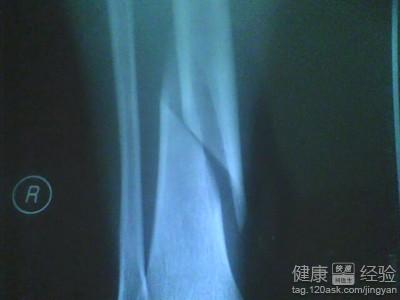

2款治愈骨折的食療偏方